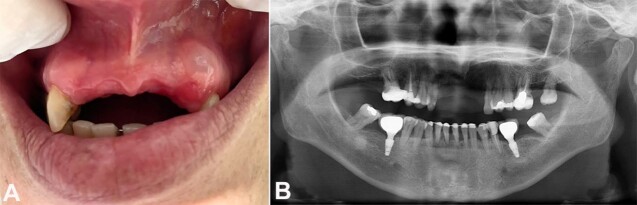

成人牙龈囊肿(GCA)是一种罕见的牙源性囊肿,占所有牙源性囊肿的0.3%。本病例报告基于CARE病例报告指南,旨在报告一例52岁女性患者,左侧前龈上部有一个症状性半透明结节,大小约6mm。行切除活检,组织学检查显示多个囊性腔,由不同厚度的鳞状上皮排列,病灶区域有结节增厚。在上皮增厚中观察到具有透明细胞质的细胞团。透明细胞PAS染色为阴性。建立了GCA的诊断。尽管罕见,但GCA在牙龈病变的鉴别诊断中应予以考虑。保守手术治疗有效,无复发迹象。

The gingival cyst of the adult (GCA) is a rare odontogenic cyst, consisting of 0.3% of all odontogenic cysts. This case report, based on CARE guidelines for case reports, aims to present a case of a 52-year-old female patient with a symptomatic translucent nodule in the upper left anterior gingiva, measuring approximately 6mm. Excisional biopsy was performed, and the histological examination revealed multiple cystic cavities lined by the squamous epithelium of varying thickness with focal areas of nodular thickenings. The presence of clusters of cells with clear cytoplasm within epithelial thickenings was observed. PAS staining was negative in clear cells. The diagnosis of the GCA was established. Despite its rarity, GCA should be considered in the differential diagnosis of gingival lesions. Conservative surgical treatment proved to be effective, with no signs of recurrence.